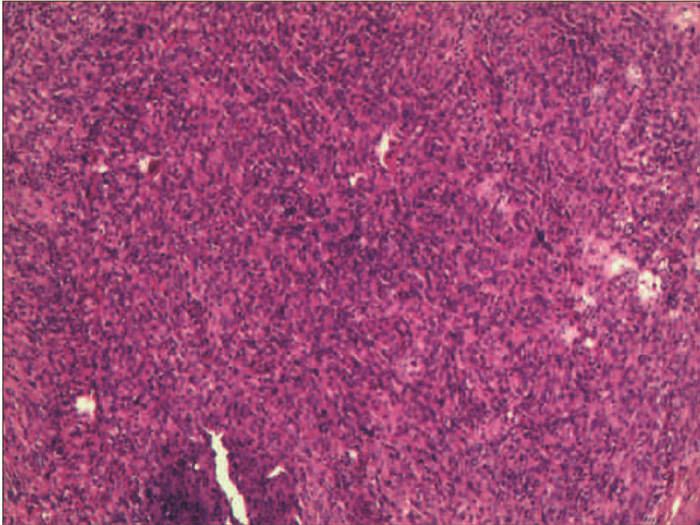

肝滤泡树突细胞肉瘤1例报告

李晨光, 贾继尧, 孙栾彪, 高硕徽

2022, 38(1): 174-176. DOI: 10.3969/j.issn.1001-5256.2022.01.029

摘要(1626) HTML (458) PDF (2854KB)(70)

摘要: